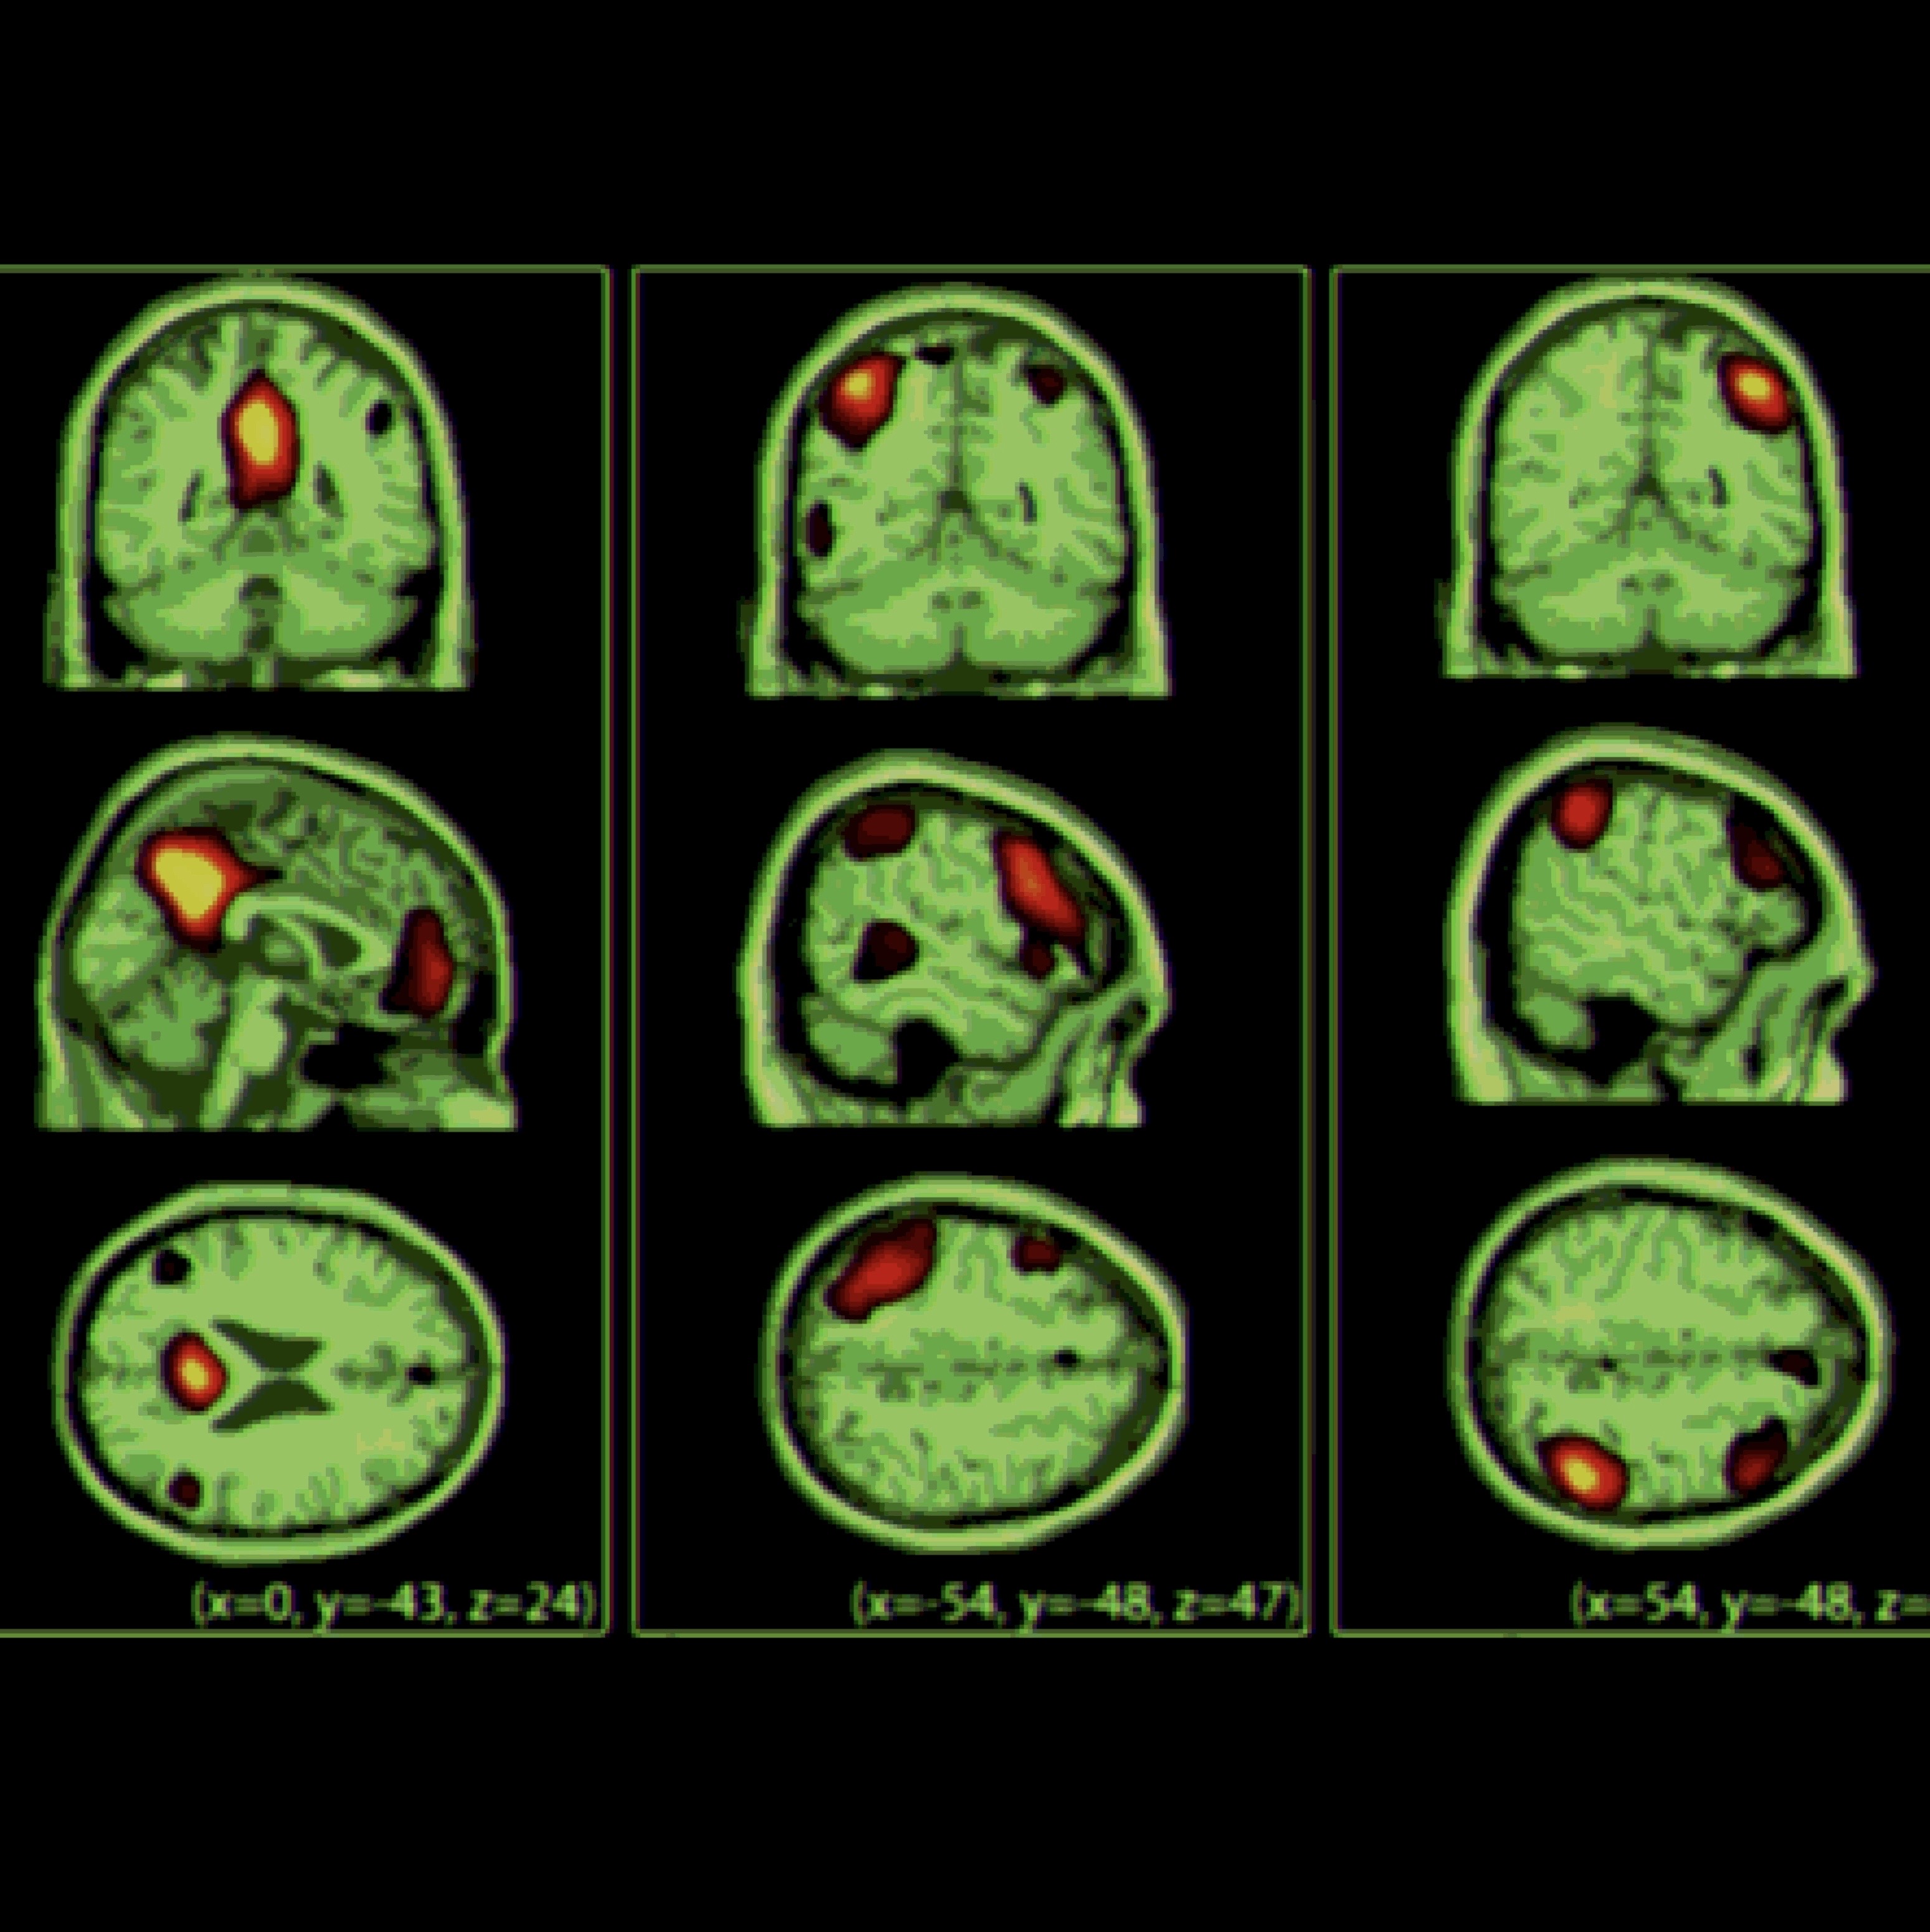

Brain data has been collected. Images of my fMRI, MRI and EEG are pictured above.

Data will be fed into training data of the AI, as well as used as a base brain. In layman's terms, the AI will build itself upon the simulated scaffolding of my brain.